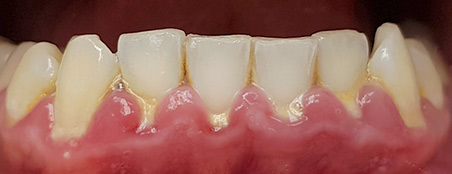

Наши работы

Перед началом лечения делаются цифровые фотоснимки полости рта. Эти съемки регулярно повторяются, чтобы фиксировать изменения в положении зубов. Еще один способ оценить масштаб проблемы – изготовить гипсовые модели челюстей, чтобы пациент мог убедиться в изменении положения зубов и общей запущенности болезни. Кроме того, на такой модели врачу удобнее проводить все необходимые измерения.